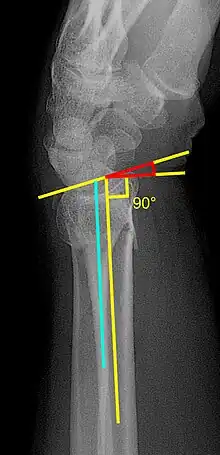

En outre, il se distingue par le développement de nouvelles procédures diagnostiques et thérapeutiques, telles que la prothèse cardan[4] ou la méthode de traitement de fractures de poignet[5].